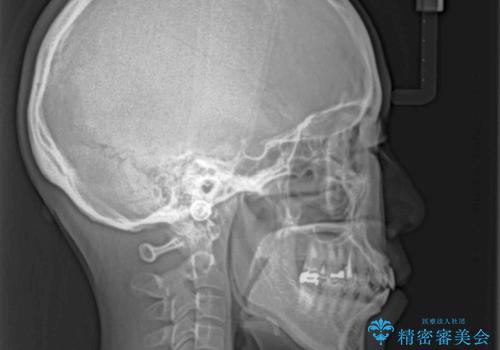

上下前歯がくちばしのように突出していたため、上下左右の第一小臼歯4本を抜歯し、ワイヤー装置にて矯正治療を行うこととしました。

上顎骨に対して下顎骨がやや前方位に位置しているため、歯肉退縮を回避するために下顎前歯をあまり内側に移動させることができない状況でしたが、十分に口元の突出感を改善することができました。